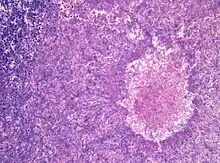

| Aspergillomas complicating tuberculosis: multiple aspergillomas within large cavitary lesions of tuberculous origin. | |